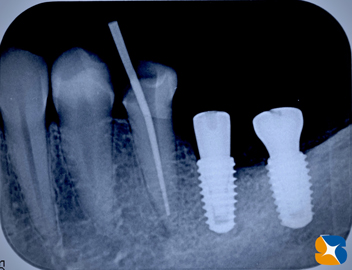

レントゲンで確認すると、かなり奥に傾いてインプラントが移植させていることが確認できます。

精密なレントゲン撮影を行うと、やはりインプラントを支える周囲の骨が、溶けて無くなっていました。

レントゲンでチェック。大きく失われていた下顎の骨も順調に再生しています。